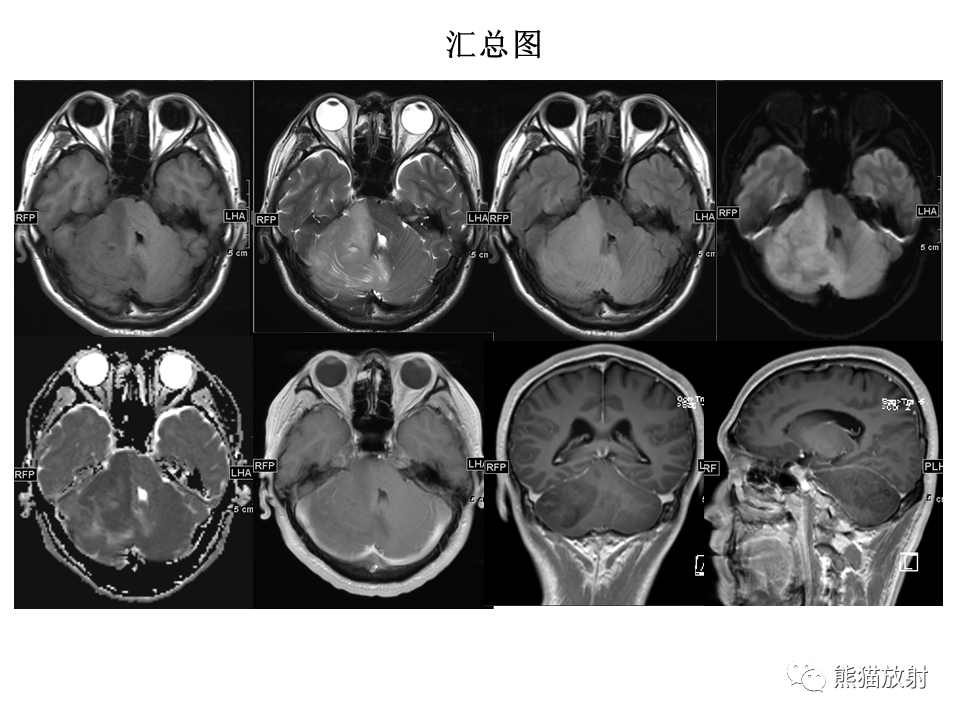

【PPT】小脑发育不良性神经节细胞瘤 VS 成人型髓母细胞瘤-3